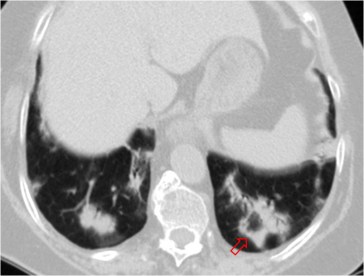

SIGNO DEL ALVEOLOGRAMA AÉREO

En la radiografía de tórax y en la TC pueden verse, en el seno de las condensaciones alveolares, pequeñas zonas de densidad aire que corresponden a alveolos libres de condensación. El alveolograma aéreo es, por tanto, signo de condensación alveolar y se ve más fácilmente en la periferia de ésta.

La imagen de TC muestra una condensación alveolar en en lóbulo inferior izquierdo con alveolograma.